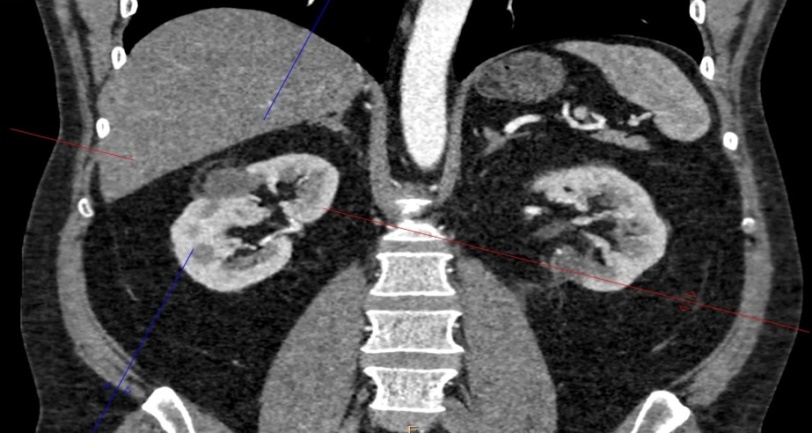

Проведен ретроспективный анализ эффективности криоаблации с 2015 по 2025 гг. у 630 пациентов больных с ПКР находящихся на лечении в ГБУ РО КДЦ «Здоровье». Возраст больных варьировал от 41 до 82 лет (средний возраст 61,5 лет). Из них 346 женщин, 284 мужчин. Критериями выбора методики криоаблации являлись наличие коморбидного статуса, конституциональные особенности и сопутствующая соматическая патология, которые ограничивали возможность выполнения органосохраняющей резекции или радикальной нефрэктомии. При этом все пациенты, независимо от возраста и пола, имели стадию T1aN0M0, а их функциональный статус по шкале ECOG составлял 0–1. Диагноз был установлен на основании клинико-рентгенологических данных (КТ почек с контрастным усилением) в соответствии с рентгенологическими критериями диагностики ПКР. Гистологическое подтверждение диагноза получали у 587 (93%) больных, остальные случаи признавались ложноотрицательным результатом. Единственная почка была у 5 больных, у 3 больных был билатеральный ПКР, в последующем такие больные получали комбинированное хирургическое лечение (рис. 3, 4).

Рисунок 4 - Снимки после комбинированной хирургии ПКР (криоаблация опухоли правой почки, резекция левой почки)